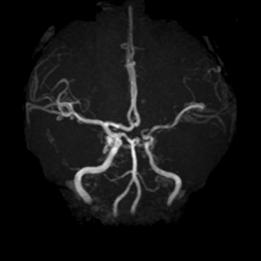

病例38:烟雾病合并右侧大脑前动脉A2段开窗畸形